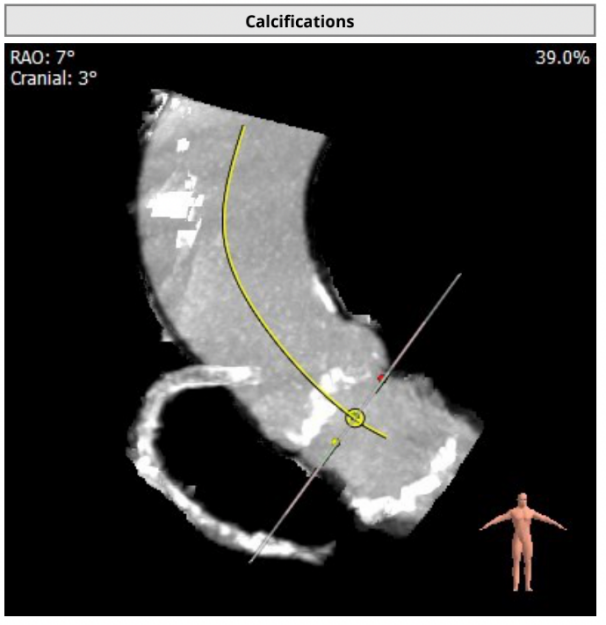

近日,武汉大学人民医院江洪教授团队成功挑战主动脉瓣严重狭窄合并钙化病变,顺利完成SAPIEN 3球囊扩张式瓣膜植入。在团队成员紧密配合下,克服患者弥漫钙化病变,顺畅完成过弓、跨瓣及释放操作,实现了手术的圆满成功。这是武汉大学人民医院首例应用SAPIEN 3瓣膜完成的TAVR。 患者基本情况 患者女性,78岁,既往有劳累性心绞痛,三支血管病变,右冠、前降支均存在大量钙化及狭窄,主动脉瓣严重狭窄伴中度钙化。 影像学检查结果 术前CT结果显示,主动脉瓣口面积373.6mm²,瓣环平均直径22.3mm,瓣环周长70.5mm;LVOT面积287.2 mm²,LVOT平均直径19.9mm;心夹角55°;左冠开口高度14.8mm、右冠开口高度16.2mm。 术前CT检查结果 手术策略讨论: